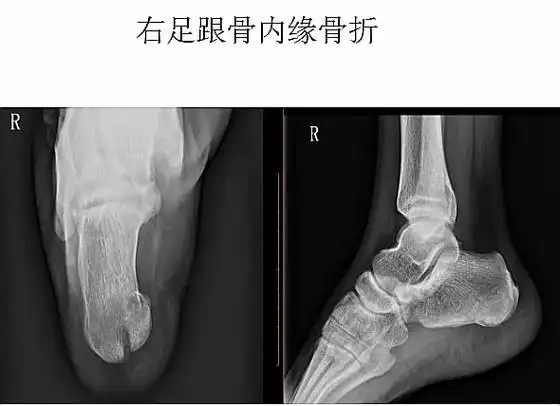

典型x线片

【原创】跟骨骨折一例报道 - 骨科与显微外科专业讨

第二张图标示的是一个正常的跟骨的一些解剖状态,它有一个正常的贝累